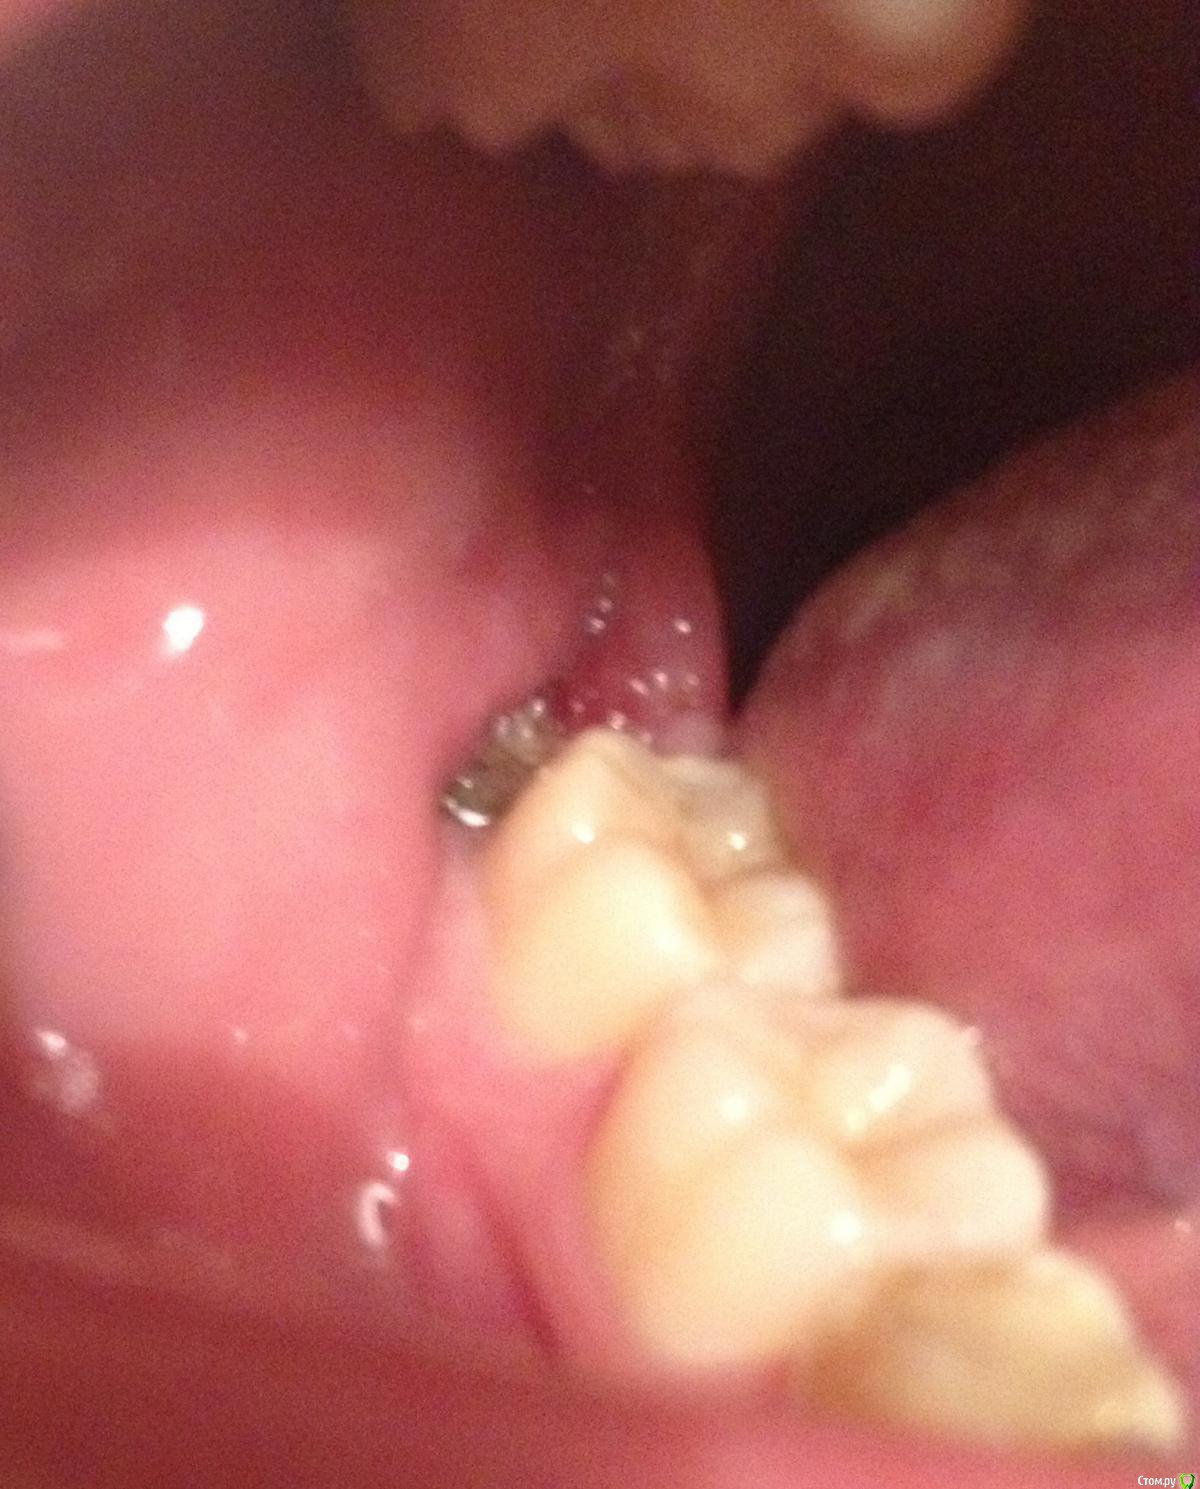

EvaBres Опубликовано 30 декабря, 2015 Автор Поделиться Опубликовано 30 декабря, 2015 За качество фото извините) как смогла, шире рот не открывается и не подлезть) Ссылка на комментарий

EvaBres Опубликовано 30 декабря, 2015 Поделиться Опубликовано 30 декабря, 2015 (изменено) Уважаемые доктора! Прошу у вас совета и мнения. История моя такова: сложное удаление ретинированного 38 зуба, с выпиливанием кости, далее хирург сделал пару шовчиков, но лунку оставил с открытым доступом и положил в нее альвеостаз, неделю ходила к нему на перевязки, каждый день менял эти жгутики на новые, говорил что зажив ленте идет хорошо, отек сошел на 3-4 сутки, боль оставалась, но периодическая и незначительная, на 7 день врач убрал швы, альвеостаз, для того чтобы перейти к заключительному этапу - формированию сгустка, пытался это сделать иглой, но нужного количества крови как я поняла не было, в итоге сгусток нормально не сформировался, врач положил в лунку рыхло альвеожил и сказал, что если заболит - сразу искать его, а если нет, то все хорошо. В этот же день ничего не болело, на следующий начало поднывать немного уже поздно вечером, а еще на следующий день мне нужно было уезжать, так я к нему и не попала. 2 дня в поезде. Теперь в общем в чем беда: лунка периодически поднывает, температуры нет, отека мягких тканей нет, десна в принципе не отечна, при пальпации болезненна, с одной стороны лунки имеется небольшое покраснение. В самой лунке налет, образовавшийся за последние 2 дня, цвет бело-серый, не могу точно понять, при нажатии на десну, сегодня с утра вытекала желтоватая жидкость. Понимаю что с 30 декабря до 4-5 января как минимум к врачу не попаду, в местной больнице выходные у него. Что можно делать в домашних условиях чтобы не усугубить процесс? Ведь я так понимаю это не норма... Изменено 30 декабря, 2015 пользователем EvaBres Ссылка на комментарий